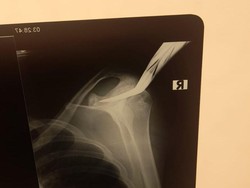

Pembacokan horor menimpa seorang remaja ojek online (ojol) berinisial TS (17) dini hari tadi. TS mengalami luka bacok hingga sebilah celurit menancap di bahu.